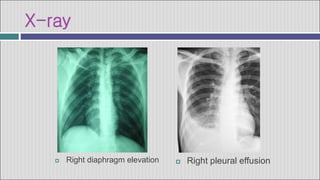

X-ray

 Right pleural effusion

 Right diaphragm elevation